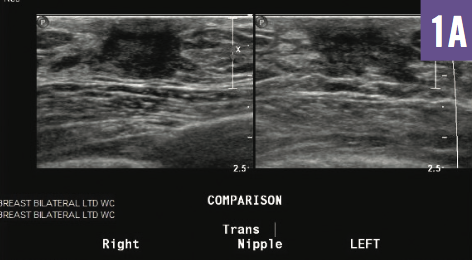

Interactive Quiz: Galactorrhea as the Initial Presentation of a Hepatic Condition